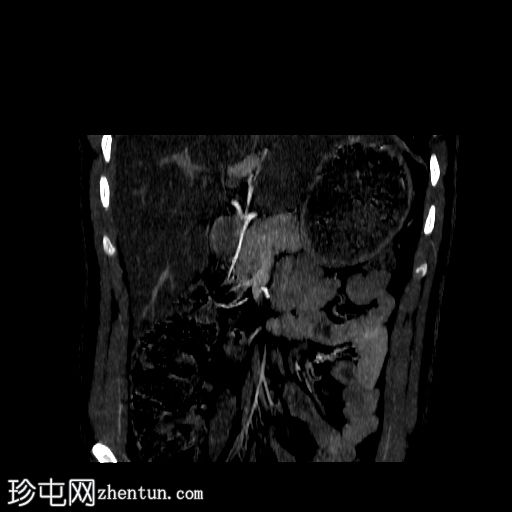

CT肾血管造影显示一条起源于左肾下段的副肾静脉,该静脉环绕主动脉走行,并接受来自腰静脉的属支,走行于主动脉后方,最终汇入下腔静脉。

本病例展示了一条环绕主动脉的副左肾静脉,其走行于主动脉后方并汇入下腔静脉,而右肾静脉解剖结构正常。

双侧肾动脉解剖结构正常,双侧肾动脉均起源于L2椎体水平的腹主动脉,管径正常,无狭窄、动脉瘤、夹层或副动脉。